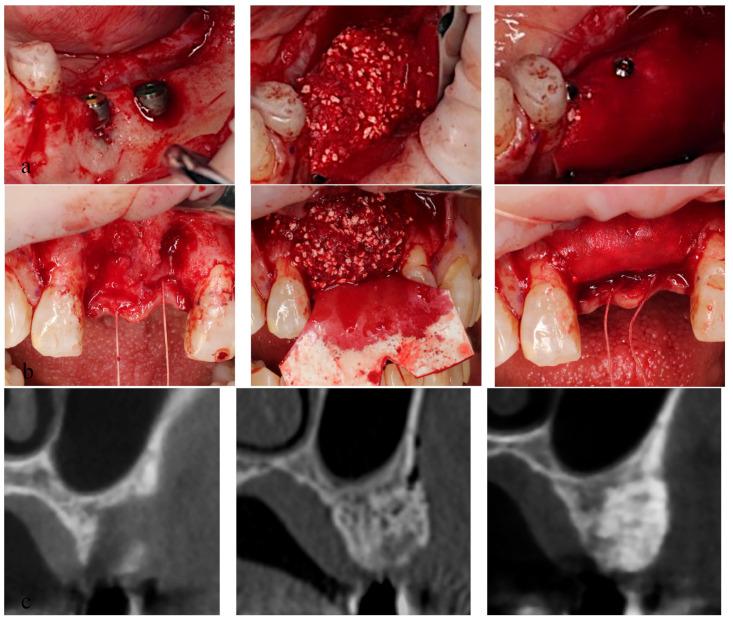

Biodegradable guided bone regeneration (GBR) membranes consist primarily of collagen and aliphatic polyesters. This study assessed the comparative efficacy of a poly(l-lactic-caprolactone) [P(LA/CL)] membrane versus that of a collagen membrane in GBR. Patients requiring GBR simultaneously or before dental implant placement in edentulous regions were randomly assigned to one of two membranes. Within each membrane, they were subdivided into 3 groups: dental implants were placed simultaneously with GBR in groups A and B, and 180 days post-GBR in group C. The augmented bone width was measured at 1, 3, and 6 mm from the implant's neck (groups A and B) or the reference line (group C), utilizing cone-beam computed tomography images, immediately and 150 days post-surgery. A histological study was performed to evaluate bone formation in group C. No adverse events were observed. In the collagen group, the absorbed ratios of the augmented bone were 40.9 ± 36.7%, 29.4 ± 30.1%, and 11.1 ± 22.0% at 1, 3, and 6 mm, respectively; the ratio at 6 mm was significantly lower than that at 1 mm ( = 0.0442). In the P(LA/CL) group, those were 26.2 ± 27.3%, 17.1 ± 19.7%, and 13.3 ± 16.4% at 1, 3, and 6 mm, respectively, with no significant difference at each point. No significant inter-membrane differences were observed. The bone augmentation potential of the P(LA/CL) membrane matched that of the collagen membrane. P(LA/CL) could be used as a safe and effective membrane in GBR.

可生物降解引导骨再生(GBR)膜主要由胶原蛋白和脂肪族聚酯组成。本研究评估了聚(L-乳酸-己内酯)[P(LA/CL)]膜与胶原蛋白膜在GBR中的相对疗效。在无牙区需要在种植体植入前或同时进行GBR的患者被随机分配到两种膜中的一种。在每种膜内,他们又被细分为3组:A组和B组在GBR同时植入牙种植体,C组在GBR后180天植入。利用锥形束计算机断层扫描图像,在手术后即刻和150天时,在距种植体颈部1、3和6 mm处(A组和B组)或参考线(C组)测量增加的骨宽度。对C组进行了组织学研究以评估骨形成情况。未观察到不良事件。在胶原蛋白组中,在1、3和6 mm处增加骨的吸收比例分别为40.9±36.7%、29.4±30.1%和11.1±22.0%;6 mm处的比例显著低于1 mm处(P = 0.0442)。在P(LA/CL)组中,在1、3和6 mm处分别为26.2±27.3%、17.1±19.7%和13.3±16.4%,各点之间无显著差异。未观察到膜间的显著差异。P(LA/CL)膜的骨增量潜力与胶原蛋白膜相当。P(LA/CL)可用作GBR中一种安全有效的膜。